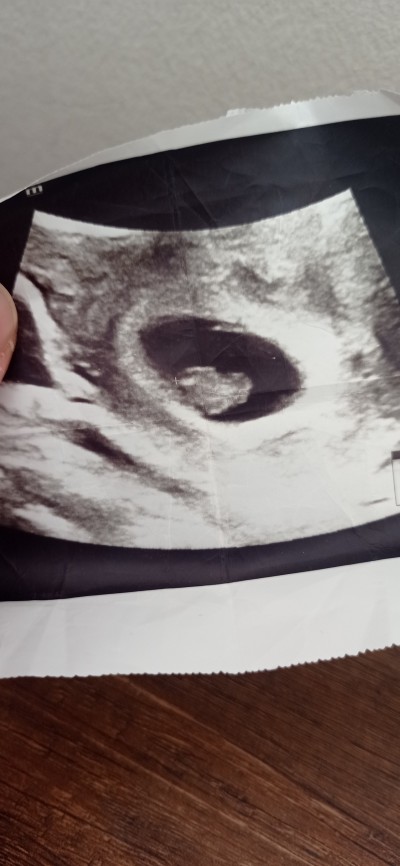

Keseye göre cinsiyet tahmini alabilir miyim 😊

Gebelik haftası 10+4

Kız bence:) canım sağlıkla gelsin